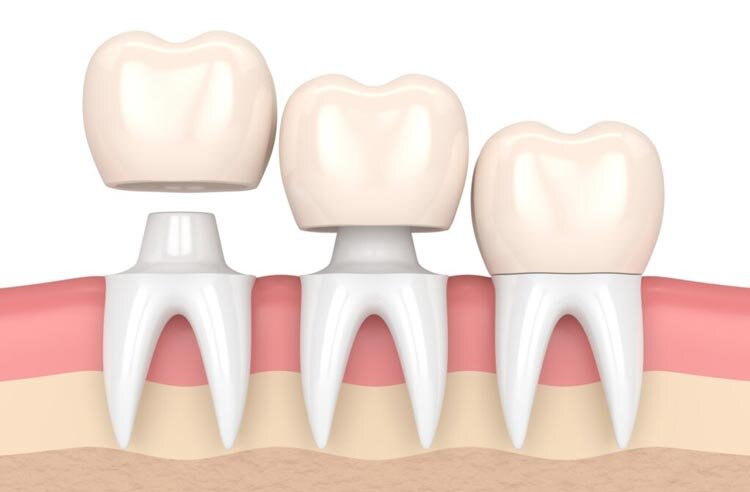

در دنیای پرهیاهوی امروز، حفظ سلامت دهان و دندان فراتر از یک ضرورت بهداشتی، به یک نیاز اساسی برای حفظ اعتمادبهنفس و کیفیت زندگی تبدیل شده است. در این میان، روکش دندان به عنوان یکی از رایجترین و مؤثرترین روشهای ترمیمی، نقش حیاتی در نجات دندانهای آسیبدیده ایفا میکند. اما شاید اولین و مهمترین سوالی که برای متقاضیان ایجاد شود، هزینه روکش دندان در سال جاری است. در این مقاله جامع، قصد داریم به تمامی ابعاد این درمان بپردازیم و با بررسی جدیدترین تعرفهها در سال ۱۴۰۴، شما را برای یک تصمیمگیری آگاهانه یاری کنیم. همچنین لازم به ذکر است که کلینیک دندانپزشکی شیان به عنوان بهترین مجموعه در این زمینه، با بهرهگیری از بروزترین متدها و تیمی از متخصصین مجرب، به عنوان یکی از معتبرترین مجموعهها در حوزه دندانپزشکی شناخته میشود و خدمات فوقالعادهای را به مراجعان محترم ارائه میدهد.

تعیین یک رقم ثابت و قطعی برای هزینه روکش دندان تقریباً غیرممکن است، زیرا این هزینه تحت تأثیر طیف وسیعی از متغیرها قرار دارد. با این حال، برای ارائه یک دیدگاه شفاف، میتوان هزینه تقریبی انواع رایج روکش را بر اساس جنس و فناوری ساخت آنها دستهبندی کرد. روکشهای فلز-سرامیک (PFM) که به دلیل استحکام و قیمت نسبتاً مناسب محبوب هستند، معمولاً در بازه قیمتی ۶,۰۰۰,۰۰۰ تا ۸,۰۰۰,۰۰۰ تومان برای هر واحد قرار دارند.

در مقابل، روکشهای تمام سرامیک مانند زیرکونیا که زیبایی و استحکام را توأمان دارند، هزینه بالاتری داشته و از ۸,۰۰۰,۰۰۰ تومان شروع شده و تا ۱۲,۰۰۰,۰۰۰ تومان نیز میرسند . جدیدترین و زیباترین نوع روکش، یعنی روکش ایمکس (E-max) که برای دندانهای جلویی ایدهآل است، گرانترین گزینه محسوب میشود و قیمت آن از ۱۰,۰۰۰,۰۰۰ تومان فراتر رفته و در برخی کلینیکهای تخصصی به ۱۵,۰۰۰,۰۰۰ تومان نیز میرسد . در نهایت، روکشهای تمام فلز و استیل ضد زنگ که بیشتر برای دندانهای آسیاب و یا به صورت موقت کاربرد دارند، ارزانترین گزینه بوده و قیمت آنها از حدود ۳,۵۰۰,۰۰۰ تومان آغاز میشود.

برای درک بهتر نوسانات هزینه روکش دندان، لازم است با جزئیات بیشتری به عوامل تأثیرگذار نگاه کنیم. اولین و مهمترین عامل، جنس و تکنولوژی ساخت روکش است. روکشهای PFM به دلیل داشتن زیرساخت فلزی، مقرونبهصرفهتر هستند اما ممکن است پس از مدتی خط تیرهای در ناحیه لثه ایجاد کنند. در مقابل، روکشهای زیرکونیا و ایمکس از نظر زیبایی شناسی در سطح بالاتری قرار دارند و برای افرادی که به فلزات حساسیت دارند یا به دنبال طبیعیترین نتیجه هستند، مناسبترند. دومین عامل، هزینه لابراتوار و دستمزد دندانپزشک است.